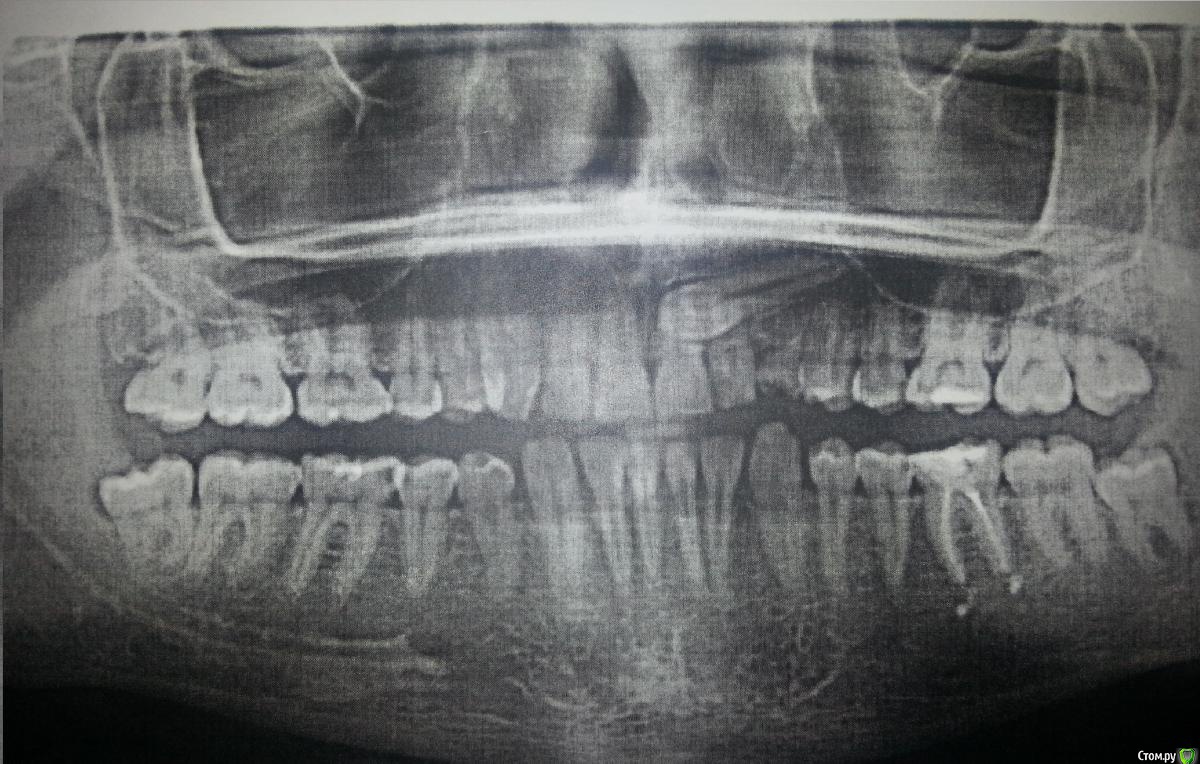

fulnik Опубликовано 3 января, 2019 Поделиться Опубликовано 3 января, 2019 (изменено) 48 частично закрыт капюшоном, 38 полностью. На счет 23 знаю, интересуют только нижние восьмерки. Нижний ряд аномалия: плотное расположение. 33 повернут. Сразу скажу, удалять 48,38 не хотелось бы, ибо имеют полностью здоровых антагонистов и если удалять, то вместе с 18,28, а на это нет ни времени ни сил.Так вот, как считаете что делать с 48,38? Изменено 3 января, 2019 пользователем fulnik Ссылка на комментарий

fulnik Опубликовано 4 января, 2019 Автор Поделиться Опубликовано 4 января, 2019 Что вы имеете ввиду?При таком положении восьмых моляров, особенно 38 операция тяжелая будет? Я приблизительно по времени и травматичности. Ссылка на комментарий

kramer Опубликовано 4 января, 2019 Поделиться Опубликовано 4 января, 2019 При таком положении восьмых моляров, особенно 38 операция тяжелая будет? Я приблизительно по времени и травматичности. Все зависит от квалификации хирурга / оснащения. Не самая сложная ситуация. Послеоперационный отек, болезненность все равно будут так или иначе 1 Ссылка на комментарий